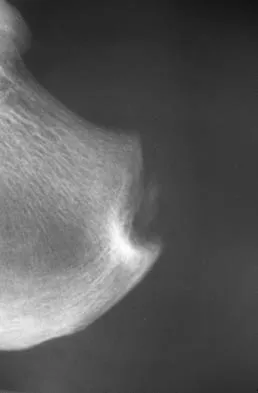

A 65-year-old man has chronic Achilles insertional tendinitis that is refractory to nonsurgical management. A radiograph is shown in Figure 9. Preoperative counseling should include a discussion of the realistic duration of postoperative recovery. You should inform the patient that his expected recovery will last

Explanation

An older patient with calcaneal enthesopathy may take a year or more to recover after tendon debridement and calcaneal ostectomy. Young patients, and those with purely tendon pathology, may recover more quickly. McGarvey WC, Palumbo RC, Baxter DE, et al: Insertional Achilles tendinitis: Surgical treatment through a central tendon splitting approach. Foot Ankle Int 2002;23:19-25.